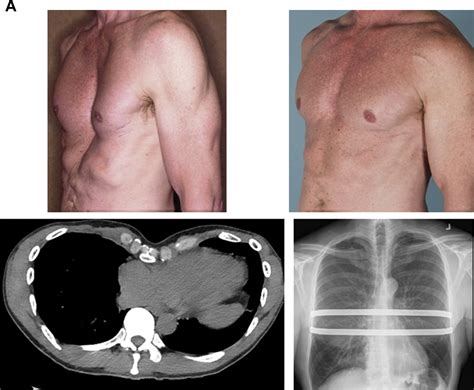

Pectus excavatum, a condition characterized by a concave or sunken chest, can significantly impact an individual's quality of life. This condition, often present from birth, can cause various physical and psychological issues. One of the most effective treatments for pectus excavatum is the Nuss Surgery Pectus Excavatum procedure. This minimally invasive surgery has revolutionized the treatment of this condition, offering patients a chance to improve their chest appearance and respiratory function.

The Nuss Surgery Pectus Excavatum procedure, also known as the Nuss procedure, is a minimally invasive surgical technique developed by Dr. Donald Nuss. This procedure involves the insertion of a concave metal bar behind the sternum to gradually push it outward, correcting the concave shape of the chest. The surgery is typically performed on adolescents and young adults, as the chest is still growing and more malleable.

The Nuss Surgery Procedure

The Nuss Surgery Pectus Excavatum procedure is generally performed under general anesthesia. The steps involved in the surgery are as follows:

• Incision: A small incision is made on the side of the chest.

• Bar Insertion: A curved metal bar is inserted behind the sternum through the incision.

• Bar Flipping: The bar is then flipped, so the convex side faces the sternum, gradually pushing it outward.

• Closure: The incision is closed with sutures, and the bar is secured in place.